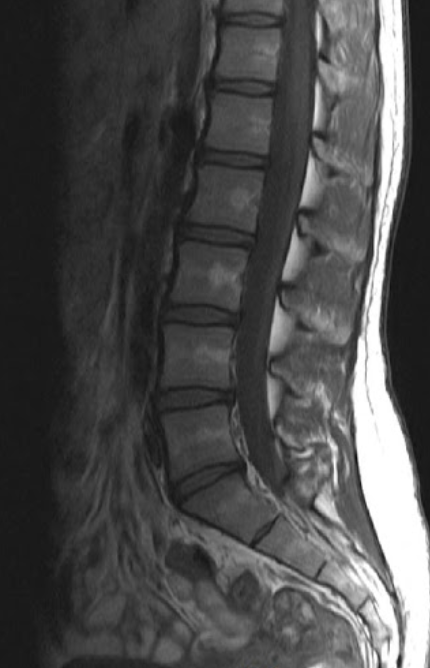

MRI 건강보험 적용